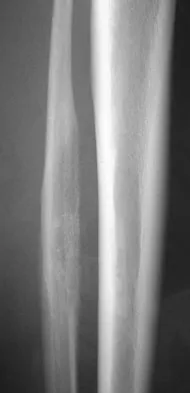

The radiographic feature seen in Figure 37 that best indicates a slow-growing process is the

Explanation

For the fibula (or any bone) to bow, a long-standing process needs to be present. Pressure from a rapid process would cause erosion, not allowing the bone to remodel. The other features are helpful confirmatory findings but also may be associated with aggressive processes. In this patient, the fibular deformity is caused by a sessile osteochondroma of the tibia. Lodwick GS, Wilson AJ, Farrell C, Virtama P, Dittrich F: Determining growth rates of focal lesions of bone from radiographs. Radiology 1980;134:577-583.